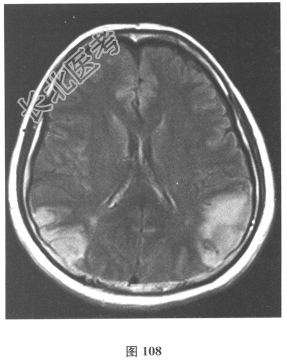

- 简答题2、脑脊液检查:常规、生化均正常,CSF-病毒TORCH(-),抗Hu、Yo、Ri均阴性,OB、MBP正常。血清抗Hu、Yo、Ri均阴性。颅脑MRI显示左颞枕、右顶枕多发长T₁、长T₂信号,Flair高信号,病变累及皮质及皮质下白质,病灶无强化,见图108~图114。根据颅脑MRI,需要鉴别的疾病应是